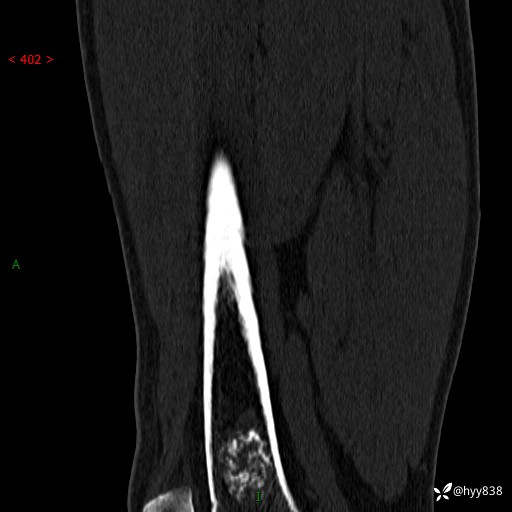

膝关节平片

img